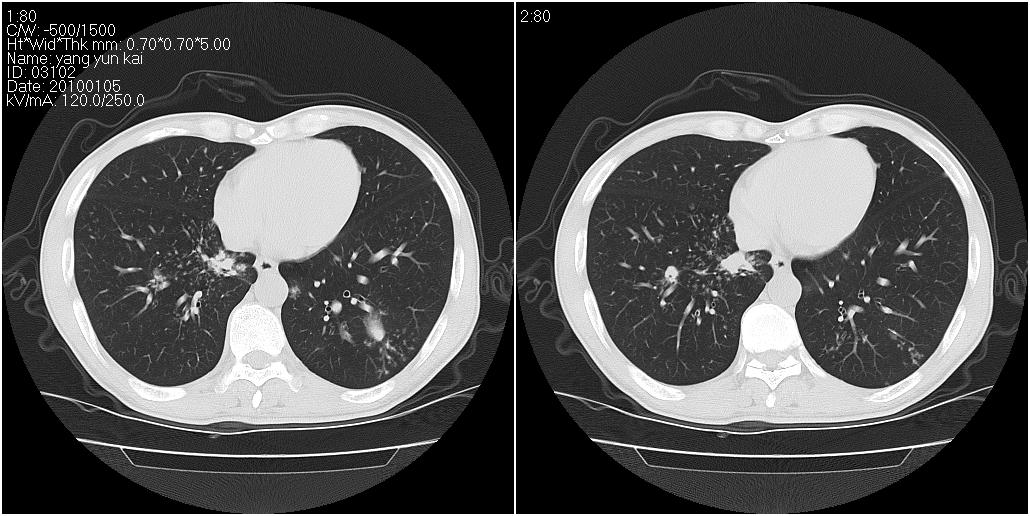

男性,47岁。近来咳痰、咳血,血沉增快(40左右),痰中未检出结核杆菌。

两肺继发性肺结核并多发性结核球形成,部分病灶内空洞形成。

符合继发性结核表现部分空洞形成并播散